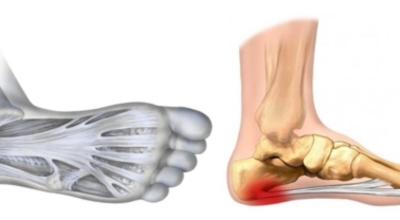

족저 근막염이란?

족저 근막이란 발가락 시작지점부터 발뒤꿈치뼈까지 발바닥 전체를 감싸고 있는 두꺼운 막을 말해요. 족저 근막은 발바닥 아치를 보존시켜 발바닥이 지면을 내딛음으로써 생기는 쇼크을 흡수하는 중요시되는 역할을 수행하고 있어요. 이 족저 근막에 일차적으로 서서히 조직 훼손이 일어나고 계속적인 활동에 의하여 염증이 커지면서 발 뒤꿈치 부근 통증을 일으키게 되는데 염증은 무리하고 반복적인 동작, 많은 활용으로 마찰에 의해 발생해요.

족저 근막염은 염증에 의한 훼손 및 통증을 유발하는 질환인데요 족저 근막염 증상은 동일한 발뒤꿈치 통증 하글런드 병변의 기형으로 알려져 있으고 아킬레스 건과 연관이 깊다고 해요. 특히 근육이 덜 풀린 아침 시간 대는 보행 시 날카롭고 바늘로 찌르는 듯한 심한 통증을 느끼게 된다고 해요. 하지만 아침 시간 대를 지나 오후에 접어들면서 일정 양 통증은 서서히 감소하기 시작한다고 하는데요 초기 증상이 나타난다면 필수로 전문의를 찾아 조기치료하는 것이 바람직해요.